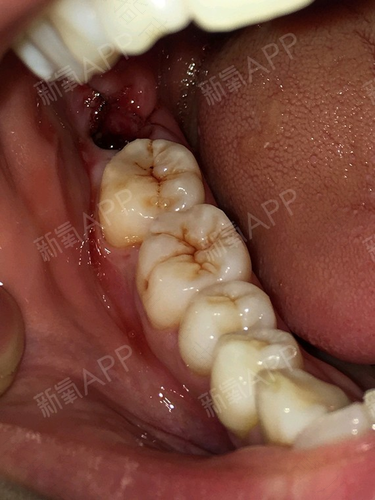

1、有疼痛感,经常会发炎的智齿:这种智齿一般是没有萌出,藏在齿槽骨里面,出现的疼痛或者是有病灶的时候,那就要消炎消肿后拔掉它。

2、智齿变成了蛀牙:而且蛀牙很严重,区域很深,这个时候一定要先治疗,根管治疗,然后拔掉它。

3、智齿的存在造成附近的牙病变:如果智齿长的位置不行,在萌出的过程中会挤歪其他牙,可能这两颗牙最后都会坏掉,所以一定要拔除才行。